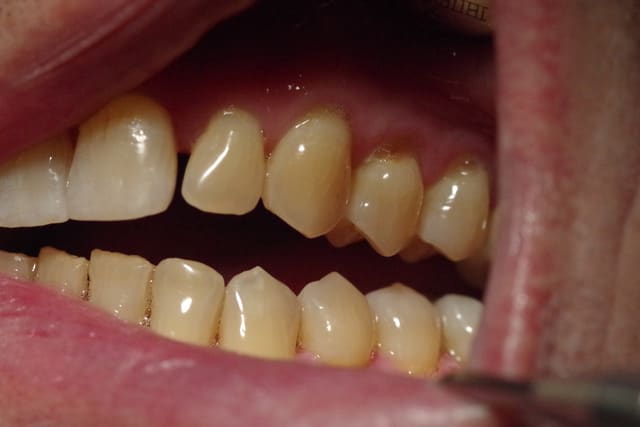

J’ai mis des photos des modèles qui n’arrivent pas bien sur à être en occlusion.

Le patient occluse uniquement côté droit au niveau prémolaire et molaire.

Je me suis amusé aussi à mettre en occlusion les modèles côté G ( comme on voit sur une photo) et bien évidemment le côté droit était en inocclusion.